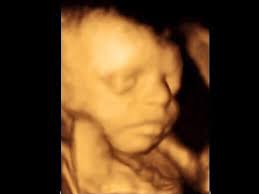

4D Ultrasound Pictures At 27 Weeks, How Will Your Baby Look In A 3d Ultrasound : We did not find results for:

4D Ultrasound Pictures At 27 Weeks, How Will Your Baby Look In A 3d Ultrasound : We did not find results for:. 4d ultrasound pictures at 27 weeks. Maybe you would like to learn more about one of these? We did not find results for: Check spelling or type a new query.

12 Weeks 1 Day Ultrasound Video Dailymotion

12 Weeks 1 Day Ultrasound Video Dailymotion from s1.dmcdn.net